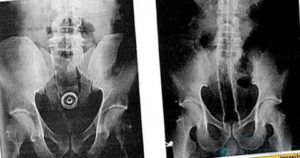

Опущение матки

Возникает у молодых и пожилых женщин. Причинами опущения матки являются тяжелые роды, врожденная патология связочного аппарата или его изнашивание с возрастом, постоянные запоры.

Изменение нормальной локализации органа провоцирует сдавливание мочевого пузыря. Пациентки также жалуются на тянущие поясничные боли, ощущение инородного тела во влагалище. Отмечается нарушение менструального цикла;

- При опущении матки рекомендуют лечебную гимнастику, упражнения Кегеля. Можно делать гинекологический массаж. Если консервативные методы оказываются неэффективными, проводят хирургическую операцию. Существует много методов лечения этой патологии.